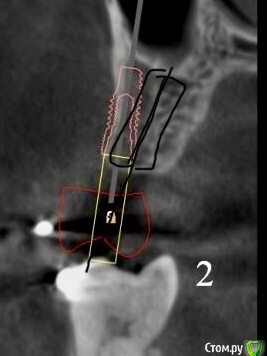

Женька Опубликовано 18 января, 2021 Поделиться Опубликовано 18 января, 2021 (изменено) Коллеги, здравствуйте!Вот такой пациент после орто. Дуги пока на месте, думаем не снимать в области отсутствующих зубов с целью удержать место до этапа протезирования.Вопрос касаемо верхнего винта.Правильно ли я понимаю, что правильным будет именно положение под цифрой 2? Хочу попробовать титановый смарт билдер, как по мне дефект как раз подходит. Или лучше мини сосиску и отсрочено в регенерат ставить. Что думаете? p.s что сверху, что снизу шестые требуют покрытия коронок, отсюда еще один вопрос, стоит ли просить ортодонта стараться ещё ангулировать 46? Просто побаиваюсь, что без этой ангуляции (если ортодонт скажет фи), не удастся сохранить зуб витальным. Ну и бонусом будет поднутрение, не получится адекватно сделать коронку и будет треугольник с едой в этой области. Изменено 18 января, 2021 пользователем Женька Ссылка на комментарий